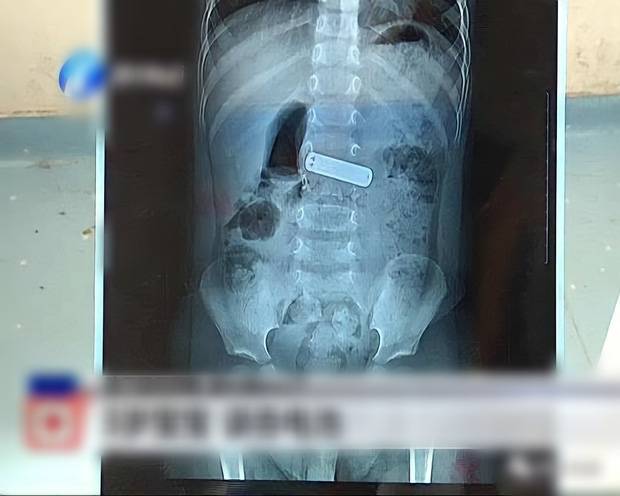

Cách đây không lâu, một bé gái 4 tuổi tên Tiểu Anh đã đến bệnh viện thăm khám. Thông qua chụp CT và nội soi dạ dày, có thể thấy một phần thịt hình cầu gồ lên trong thực quản, trông giống như một khối u.

"Sau nhiều lần kiểm tra và thảo luận đa ngành, bao gồm cả nội soi dạ dày, tôi dùng một con dao mỏng như kim để rạch phần thịt kỳ lạ và phát hiện bên trong viên thịt có một nắp nhựa màu trắng dài khoảng 2cm, làm tắc thực quản. Đó là một dị vật mắc kẹt trong thực quản quá lâu, khiến mô hạt cục bộ tăng sinh và hình thành." - Bác sĩ Phương Doanh nhớ lại.

Cho đến khi gắp dị vật ra ngoài, phụ huynh chỉ nhớ con mình đã từng tiếp xúc với dị vật liên quan cách đó chừng 4 tháng.

Sau khi được điều trị thêm, bé gái đã dần hồi phục và có thể ăn uống bình thường. Bác sĩ Phương Doanh nhấn mạnh rằng, nếu bố mẹ phát hiện ra đứa trẻ nuốt phải dị vật thì cần đến bệnh viện kiểm tra kịp thời. Lúc ấy, cơn đau và việc điều trị của đứa trẻ sẽ bớt khó khăn hơn.